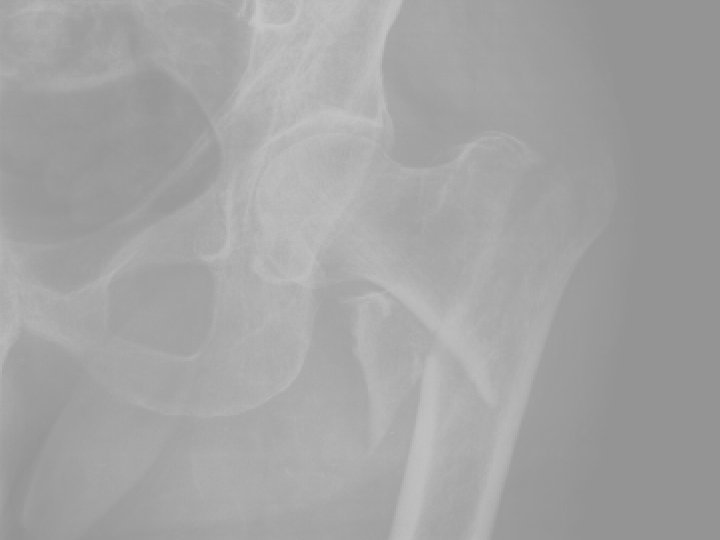

5. Medence, csípótáji törések. Az időskori sérülések halálos szövődményei több mint 50%-ban ebből a csoportból kerülnek ki. > peremtörés, szemérem- és az ülőcsont szártörései, Konzervatív kezelés < transacetabularis törések Operatív/konzervatív kezelés

5. Medence, csípótáji törések A csípőtáji törések a leggyakrabban előforduló időskori törések. A tokon belüli törés szövődménye a fejelhalás, ami az esetek 25 -35 %-ában bekövetkezik. A tokon kívüli törések gyógyhajlama jó. A leggyakoribb szövődmény a thromboembolia, mely a az első postoperatív évben 20 -25%-os halálozással jár.